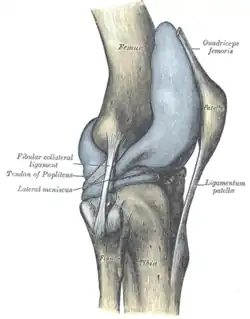

Staw kolanowy (łac. articulatio genus) – w anatomii człowieka staw kończyny dolnej, będący największym stawem ciała człowieka[1]. Jest to staw złożony (zawiasowy zmodyfikowany) – łączą się tu kość udowa i kość piszczelowa (kość strzałkowa nie buduje stawu kolanowego). Staw współtworzy trzeszczka w postaci rzepki. Staw posiada dwie łącznotkankowe łąkotki dopasowujące do siebie powierzchnie stawowe w czasie ruchów. Funkcjonalnie jest to staw zawiasowy, umożliwiający ruchy zginania i prostowania, ale w zgięciu (z wyjątkiem maksymalnego) możliwe są również ruchy rotacyjne. Wzmocniony jest więzadłami zewnętrznymi (pobocznymi oraz torebki stawowej) oraz dodatkowo bardzo silnymi więzadłami wewnętrznymi – więzadłem krzyżowym przednim i tylnym.

W stawie kolanowym łączą się trzy elementy, w tym dwie kości: kość udowa, kość piszczelowa oraz trzeszczka czyli rzepka. Główkę stawu tworzą wypukłe kłykcie kości udowej, natomiast jego panewkę lekko wklęsłe kłykcie kości piszczelowej i powierzchnie stawowe rzepki.

Łąkotki (łac. menisci) to dwa elastyczne twory, zbudowane z tkanki chrzęstnej włóknistej leżące pomiędzy kością udową a piszczelową, będące elementami dodatkowymi stawu kolanowego. Wyróżnia się łąkotkę boczną i łąkotkę przyśrodkową, nieco różniące się wielkością. Ich zadanie polega na pogłębieniu i dopasowaniu do siebie powierzchni stawowych stawu kolanowego (pomiędzy kością udową a piszczelową), a także na umożliwieniu ruchów obrotowych w zgiętym stawie kolanowym, poprzez przesuwanie się ich na powierzchni stawowej górnej kości piszczelowej.

Układ więzadłowy

Ze względu na duże siły przenoszone przez staw kolanowy jego torebka stawowa wzmocniona jest wieloma więzadłami. Dodatkową stabilizację zapewniają więzadła krzyżowe i więzadła powiązane z łąkotkami, otoczone przez torebkę włóknistą. Z tego względu w stawie kolanowym wyróżnia się więzadła zewnętrzne i więzadła wewnętrzne.